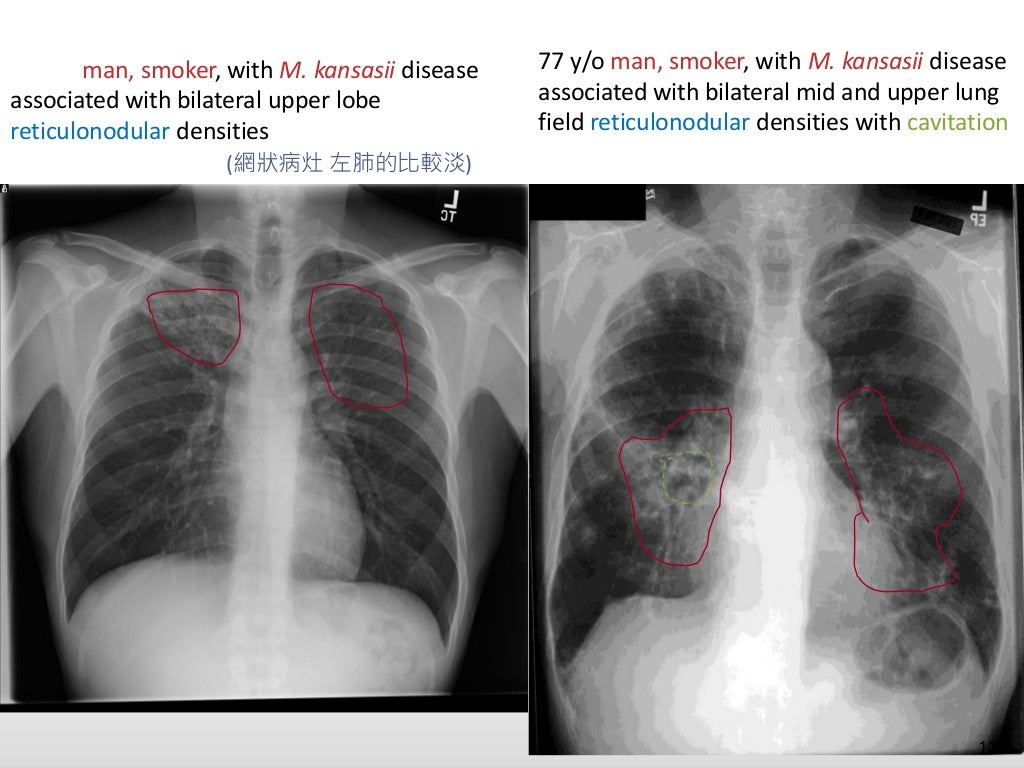

Chest imaging of ntm pulmonary disease2 How To Diagnosis Chest X-Ray It covers normal anatomy, variants, systematic approach,. Learn how a gp may diagnose copd based on your symptoms, smoking history, bmi and breathing tests. Airway, breathing, cardiac, diaphragm and everything else. Find out about the different. It can help doctors diagnose heart or lung problems, or prepare for surgery. Learn how to assess an adult with a suspected chest infection. How To Diagnosis Chest X-Ray.